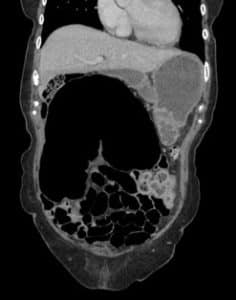

Blood investigations revealed a C-reactive protein (CRP) of 56 mg/L, with no leucocytosis or abnormalities in arterial blood gases. A subsequent abdominal computed tomography (CT) scan showed a loop of bowel with characteristic “coffee bean” morphology extending from the right iliac fossa towards the left upper quadrant, containing formed stool and gas, consistent with a diagnosis of caecal volvulus (Figure 1).

Figure 1. CT images of the abdomen showing the “coffee bean” morphology indicative of caecal volvulus

Rectal prolapse and abdominal pain occurring together may be indicative of various underlying conditions. Chronic constipation can weaken the supportive tissues of the rectum, leading to prolapse, while the straining associated with constipation can also cause abdominal discomfort. [10] Pelvic floor dysfunction, characterized by weakness or coordination issues in the pelvic muscles, can contribute to both prolapse and abdominal discomfort.[11] Complications of rectal prolapse, such as incarceration or strangulation, can lead to significant abdominal pain requiring urgent medical attention.[12] Inflammatory bowel diseases like Crohn’s disease or ulcerative colitis may cause inflammation and damage in the rectum and colon, resulting in both prolapse and abdominal pain.[13] Additionally, pelvic inflammatory conditions, neurological disorders affecting bowel function, tumours, or masses in the pelvic or abdominal region, and traumatic injuries to the pelvic area can all contribute to the simultaneous occurrence of rectal prolapse and abdominal pain.[9,15,16,17] However, the characteristic CT findings, particularly the “coffee bean” sign, led to the definitive diagnosis of caecal volvulus. While these conditions were initially considered, the CT findings ultimately ruled them out in favour of the diagnosis of caecal volvulus.[6,7]

Prompt diagnosis and intervention are paramount in managing such cases to prevent complications like bowel ischemia and necrosis. In this instance, timely surgical consultation and imaging studies, particularly a CT scan, facilitated accurate diagnosis and appropriate management. The CT findings, including the characteristic “coffee bean” sign indicative of caecal volvulus, effectively guided the surgical team in planning the intervention. While the CT scan is a valuable diagnostic tool, it is essential to acknowledge that there may be limitations or potential pitfalls in its interpretation, particularly in rare presentations such as this one.[6,7]